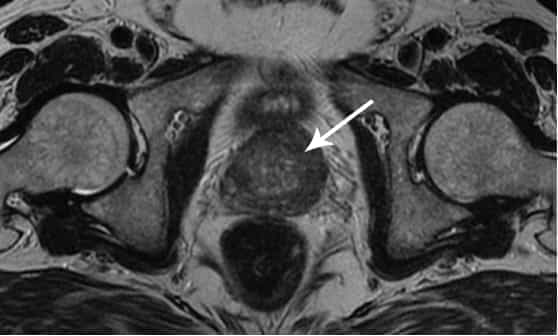

Chciałabym pokazać wam kilka zdjęć, żebyście na własne oczy przekonali się, co dzieje się z układem moczowo-płciowym i innymi organami mężczyzn, którzy nie uprawiają seksu.

Tak wygląda zapalenie gruczołu krokowego wywołane zastojem spermy (gdy jądra nie są opróżniane). Utrzymujący się stan zapalny prowadzi do łagodnego rozrostu prostaty, a następnie do raka (według statystyk, 38% mężczyzn umiera z jego powodu). Zawsze tak się dzieje w przypadku braku seksu i dlatego łagodny rozrost prostaty nazywany jest chorobą ludzi starszych.

Rak gruczołu krokowego u mężczyzny w wieku 58 lat. Przyczyna – wydłużająca się abstynencja (od około 51 roku życia). Pacjent zmarł.